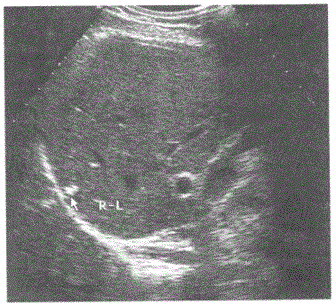

请指出下图箭头所指是何种声像图伪像:A.旁瓣伪像B.多重反射C.镜面伪像D.混响伪像

问题 请指出下图箭头所指是何种声像图伪像:

选项 A.旁瓣伪像 B.多重反射 C.镜面伪像 D.混响伪像

答案 C